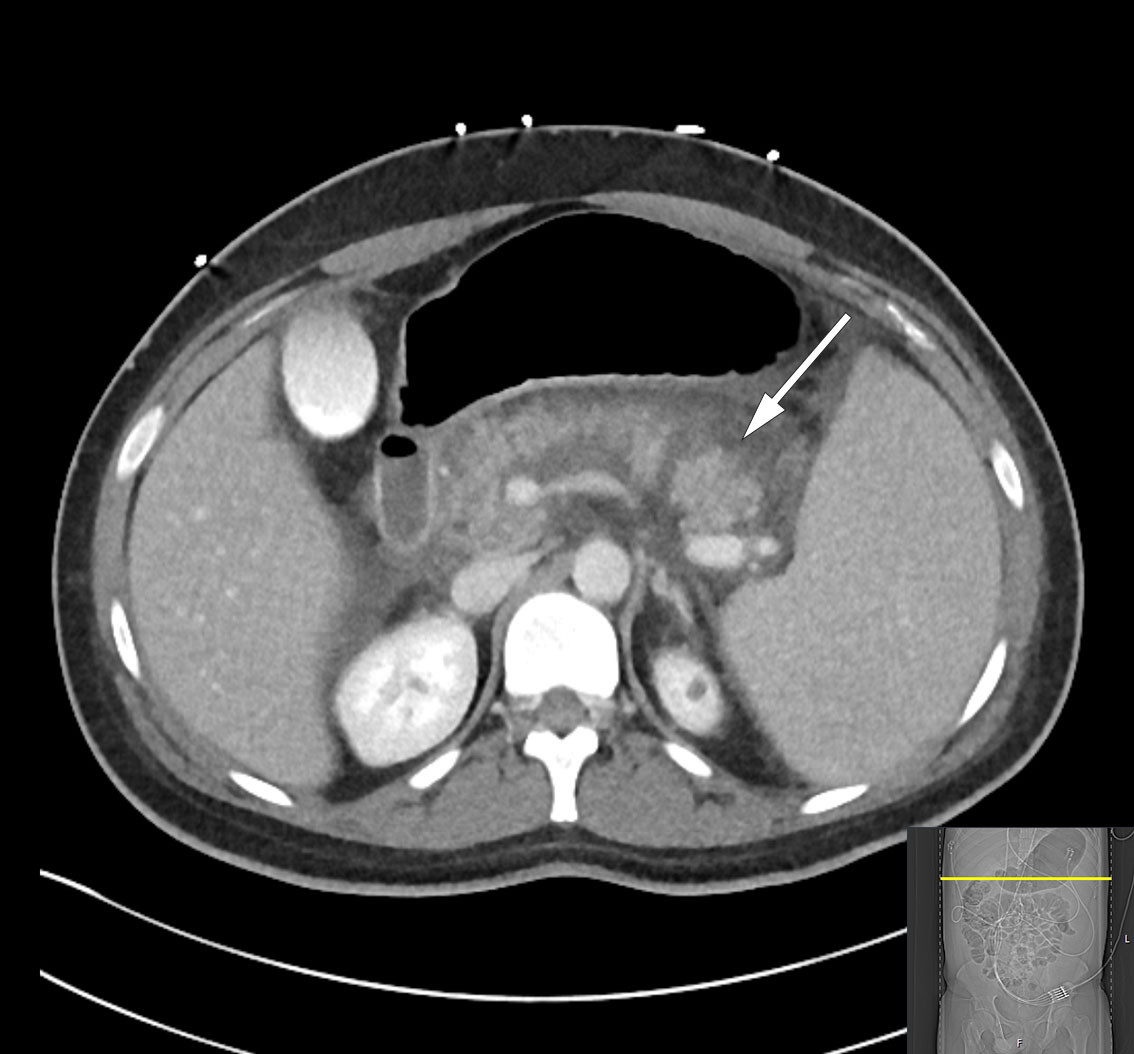

Over the course of day 3, the patient's clinical condition deteriorated further and he developed severe abdominal pain. He was transferred to the intensive care unit due to incipient organ failure with a need for oxygen. He was somnolent and, although breathing independently, required 2–3 L of O2 via nasal catheter to maintain oxygen saturation above 92 %. His INR level had increased to 1.9 while his albumin level had fallen to 22 g/L (from 45.6 g/L), raising suspicion of a bleeding disorder. In addition, his bilirubin level had increased once again to 290 μmol/L, but in the absence of any other liver or bile enzyme increases, it was decided based on an interdisciplinary discussion not to proceed immediately with another ERC examination. Further diagnostic imaging with a CT scan of the abdomen and pelvis revealed necrotising pancreatitis with peripancreatic fluid collections and free fluid in the abdomen (Figure 2). There were no signs of intra- or extrahepatic cholestasis. However, bilateral pleural effusion and atelectasis were observed, which could explain the deterioration in respiratory function. Due to the patient's elevated INR level, a pleural tap was not performed. Enlargement of the spleen (21 cm in length) was also noted.

Necrotising pancreatitis is a serious complication of acute pancreatitis and is usually associated with a prolonged and severe clinical course. Necrosis in the pancreatic parenchyma or peripancreatic tissue occurs in 5–10 % of patients with pancreatitis and rarely remains confined to the pancreas (1). Secondary infection of necroses due to bacterial translocation from the gastrointestinal tract is not uncommon, but rarely occurs within the first week. Infection should be suspected when extraluminal gas is visible within the pancreas or in surrounding tissues on CT; broad-spectrum antibiotic treatment is then indicated. Necrosectomy to remove dead tissue is only considered appropriate from 3–4 weeks into the disease course, using a step-up approach with increasing invasiveness (3).